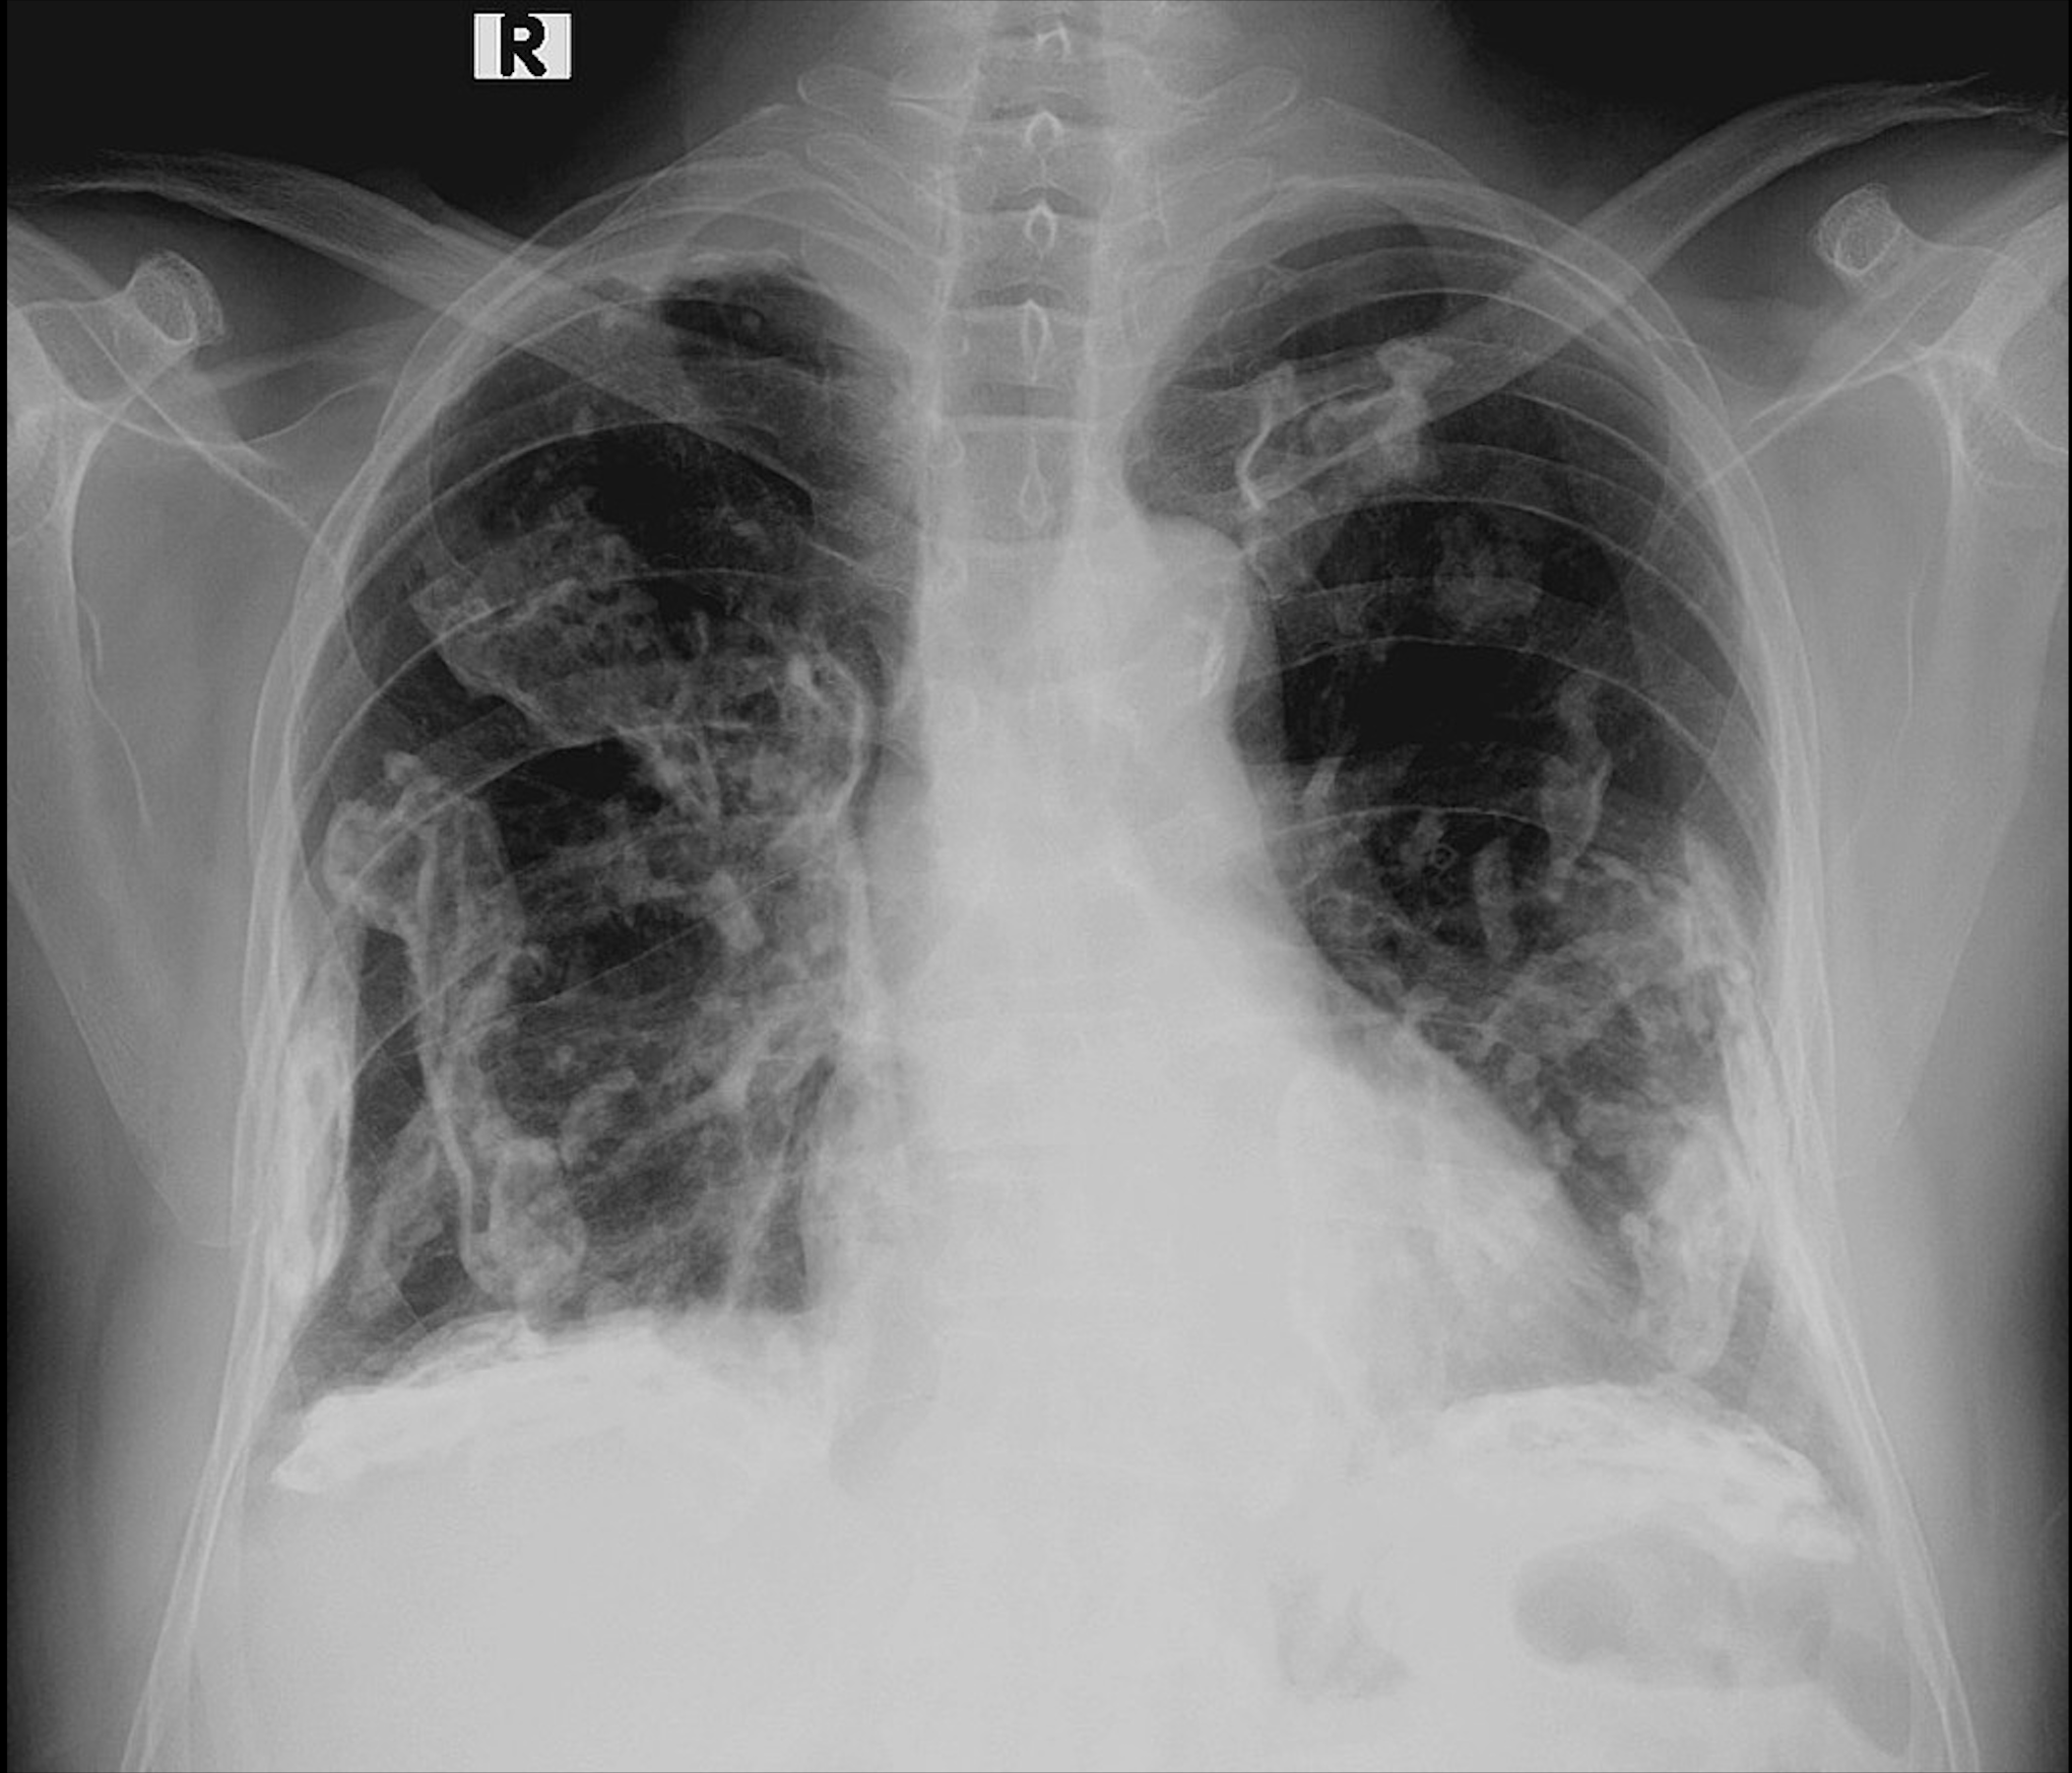

Aspect de rayon de miel

Définition : l’aspect en rayon de miel, également connu sous le terme anglais “honeycombing”, se caractérise par la présence de multiples petites cavités kystiques, organisées en plusieurs couches, séparées par des parois épaissies. On peut également observer un motif en forme de nid-d’abeilles. Cet aspect est identifiable sur les images obtenues par scanner thoracique en fenêtre […]